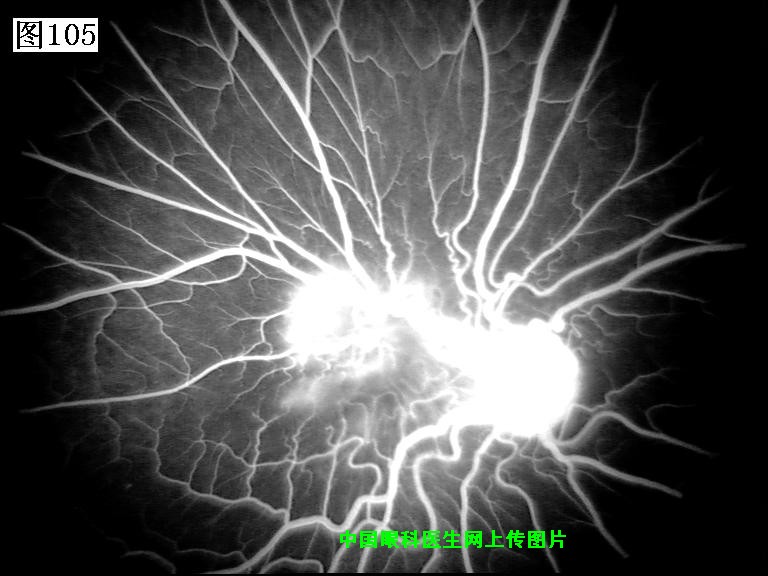

105 106 107 108